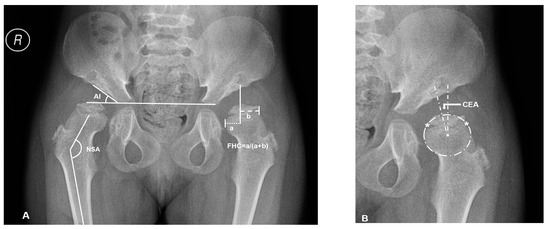

2.1. Radiographic Measurements and Analysis